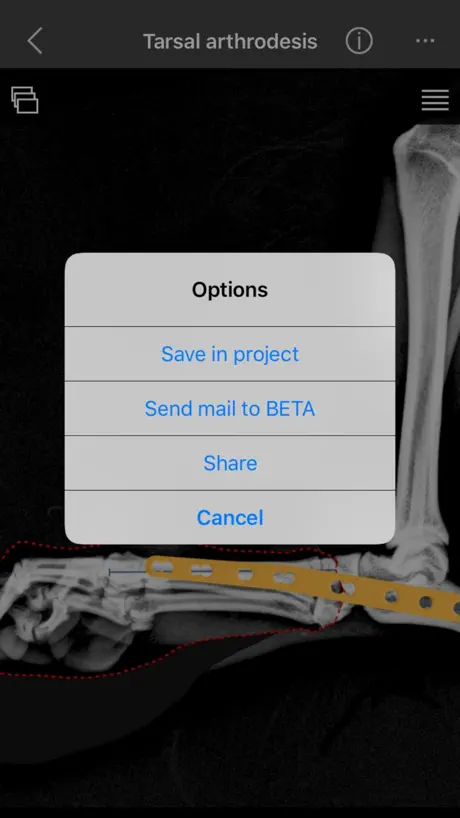

j) Pantarsal arthodesis plates

k) Partial tarsal arthodesis plates

5. Share your results

6. Save in project

a) If you have any doubt, direct contact options with a knowledgeable support team to assist the virtual planning are include in the BETA app.

j) Pantarsal arthodesis plates

k) Partial tarsal arthodesis plates

5. Share your results

6. Save in project

a) If you have any doubt, direct contact options with a knowledgeable support team to assist the virtual planning are include in the BETA app.